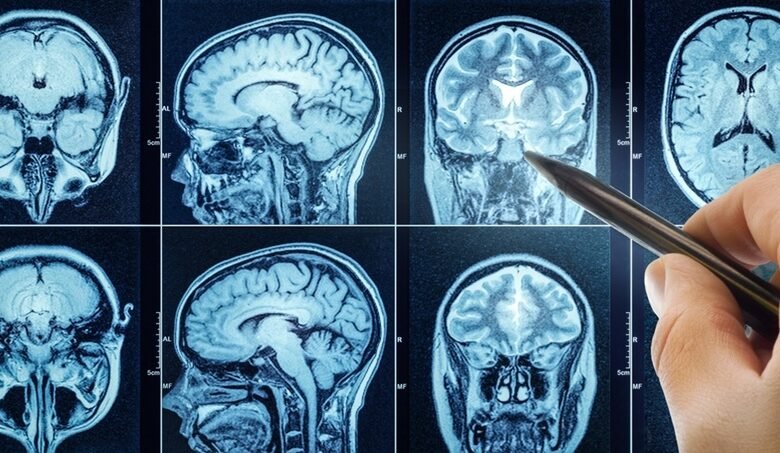

Researchers have developed a groundbreaking brain scanning method that may detect indicators of Alzheimer’s disease, years prior to the onset of symptoms. Employing a method known as cortical disarray measurement (CDM), which examines MRI scans to identify more subtle indicators of neurodegeneration, researchers aim to assist millions worried about dementia.

At present, physicians identify conditions such as dementia by utilizing a mix of surveys that indicate memory issues along with MRI imaging. Nonetheless, this procedure indicates that individuals are identified only after the illness has advanced.

With the new “precision diagnostic tool,” physicians will be able to detect disturbances in the cortex’s structure and function, especially those linked to abilities like memory, decision-making, and language.

CDM Insights analyzes clinical MRI scan data obtained from 1.5T and 3T scanners. It subsequently provides results in the shapes of images and numerical figures, typically shown as percentiles of a standard population distribution.